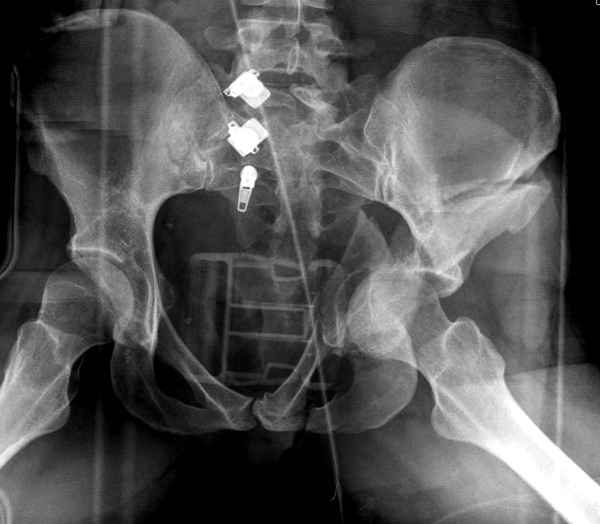

Из того минимума, что представлено, мне кажется, мы имеем дело с двухколонным переломом вертлужной впадины. Обычно медиальный (центральный) "вывих" головки встречаются в сложных двухколонных переломах со смещением.

По-моему, надо готовить больного к будущей артропластике, но без опоры на задний столб невозможно удержать протез. Опорная конструкция (кольца и т.д.) должны иметь опору, и поэтому мы бы сделали реостеосинтез задним доступом. При надобности остеотомия и рутинная фиксация с межколонными винтами.

В дальнейшем, время покажет, когда приступить к артропластике....